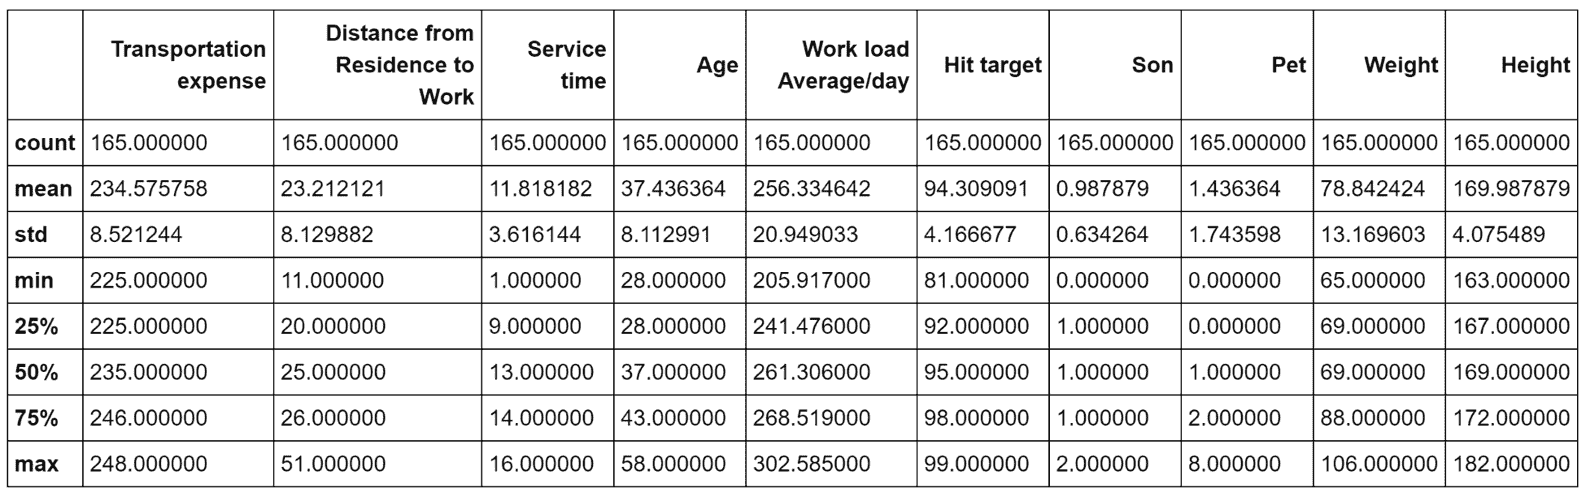

下载后(如技术要求部分所述),CSV 文件必须放在我们通常表示为<data_folder>的文件夹中。 第一步是加载数据集,并通过 Pandas DataFrame暴露的函数describe()进行全局统计分析,如下所示:

我强烈建议使用 Jupyter 笔记本(在这种情况下,命令必须仅是df.describe()),所有命令都将产生内联输出。 出于实际原因,在以下屏幕截图中,显示了表格输出的第一部分(包含八个属性):

数据集前八个属性的统计报告

当然,即使我们仅将注意力集中在子集上,我也请读者检查所有属性的值。 特别是,我们需要观察前八个属性之间存在的不同尺度。 标准差的范围是 0.01 到 350,这意味着仅由于一个或两个属性,许多向量可能极其相似。 另一方面,使用方差缩放对值进行归一化将赋予所有属性相同的责任(例如143.5和2501之间的界限为area_mean,而0.05和smoothness_mean之间的界限为smoothness_mean。 强迫它们具有相同的方差会影响因素的生物学影响,并且由于我们没有任何具体的指示,因此我们没有授权做出这样的选择)。 显然,某些属性在聚类过程中将具有更高的权重,我们将它们的主要影响视为与上下文相关的条件。